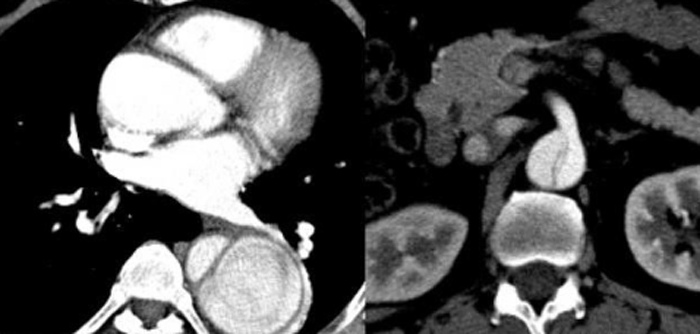

亲眼目睹患者死亡的实习护士,一时之间不知道该怎么平复自己的情绪。大叔被送来时,看起来只是后背有点疼痛,除此之外没有别的严重症状。但护士不知道的是,他患有主动脉夹层,这是一种很严重的疾病。

同事出于职业本能,马上察觉到这可能是主动脉夹层。果然,随后的血压测量证实了这一点,左右手血压差居然高达28mmHg。

在极短时间内出现胸部、背部以及腹部疼痛,并且愈演愈烈,甚至演变为撕裂般疼痛,可能是急性主动脉夹层。需要注意的是,这种疼痛往往是从前胸先开始,并延伸到后背。